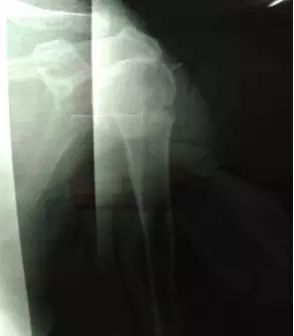

鮑阿婆年紀(jì)大了,體質(zhì)又差,難以承受手法復(fù)位的巨大痛苦,因此在幫鮑阿婆完善相關(guān)檢查后,正骨科醫(yī)生專(zhuān)門(mén)進(jìn)行了病歷討論,制定了周密的手法整復(fù)方案。在入院后第二天,就在臂叢麻醉下給予手法整復(fù)。雖然阿婆的骨折嚴(yán)重,手法復(fù)位困難太大,但正骨科醫(yī)生憑借自己精湛的醫(yī)術(shù)及豐富的臨床經(jīng)驗(yàn),順利的幫助鮑阿婆把骨折位置復(fù)好了。

整復(fù)后復(fù)查X線片,骨折端位置良好。

鮑阿婆及家人看過(guò)片子后也十分滿意,“都說(shuō)廣安醫(yī)院醫(yī)生的技術(shù)真是好,早知道3年前右手骨折在你們這里看,就不用吃那么多苦了”。鮑阿婆表示。

整復(fù)后